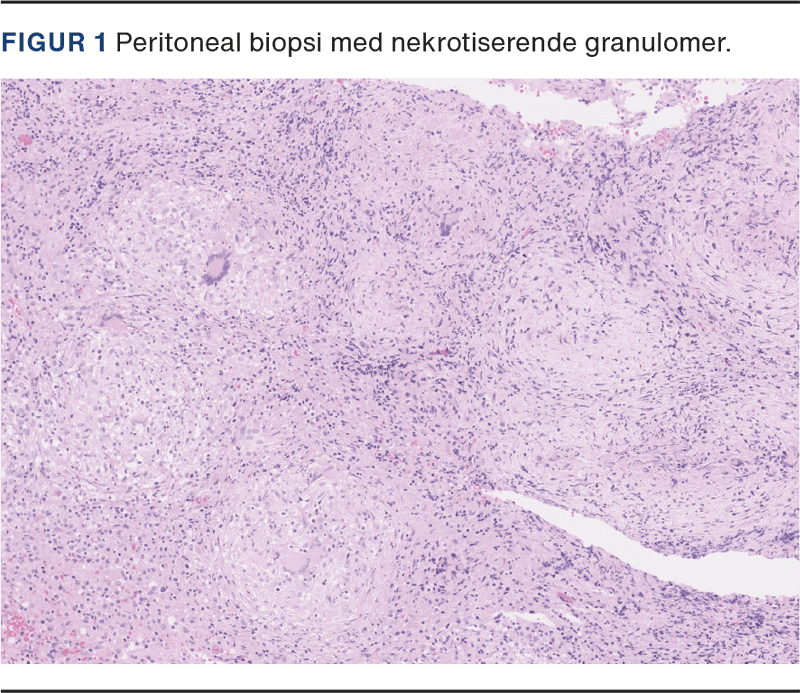

Biopsier fra laparoskopien viste nekrotiserende granulomatøs inflammation (Figur 1) samt fund af én syrefast stav, og kort tid efter fremkom dyrkningen af biopsien positiv for M. tuberculosis, der viste sig at være fuldt følsom for den givne eradikationsbehandling.